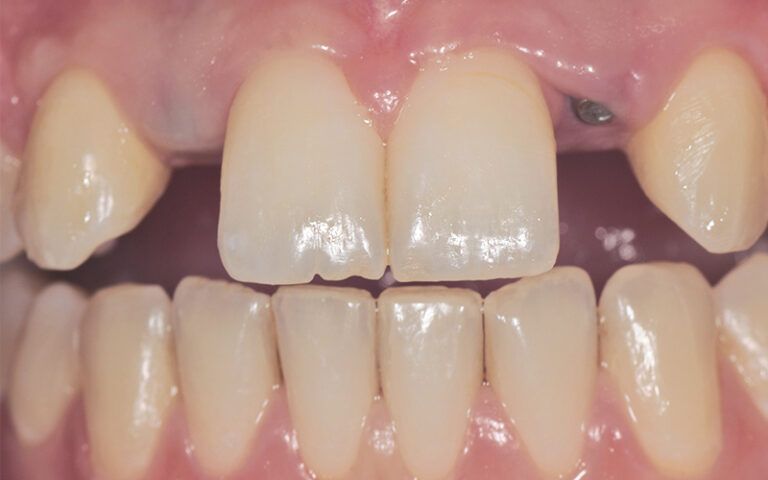

Images of the osseointegration period of the implants and healing of the tissues Images of the osseointegration period of the implants and healing of the tissues Images of the osseointegration period of the implants and healing of the tissues Images of the osseointegration period of the implants and healing of the tissues

After three months of osseointegration, the second surgery performed on both implants and the digital impressions were taken with the TRIOS (3Shape) intraoral scanner.